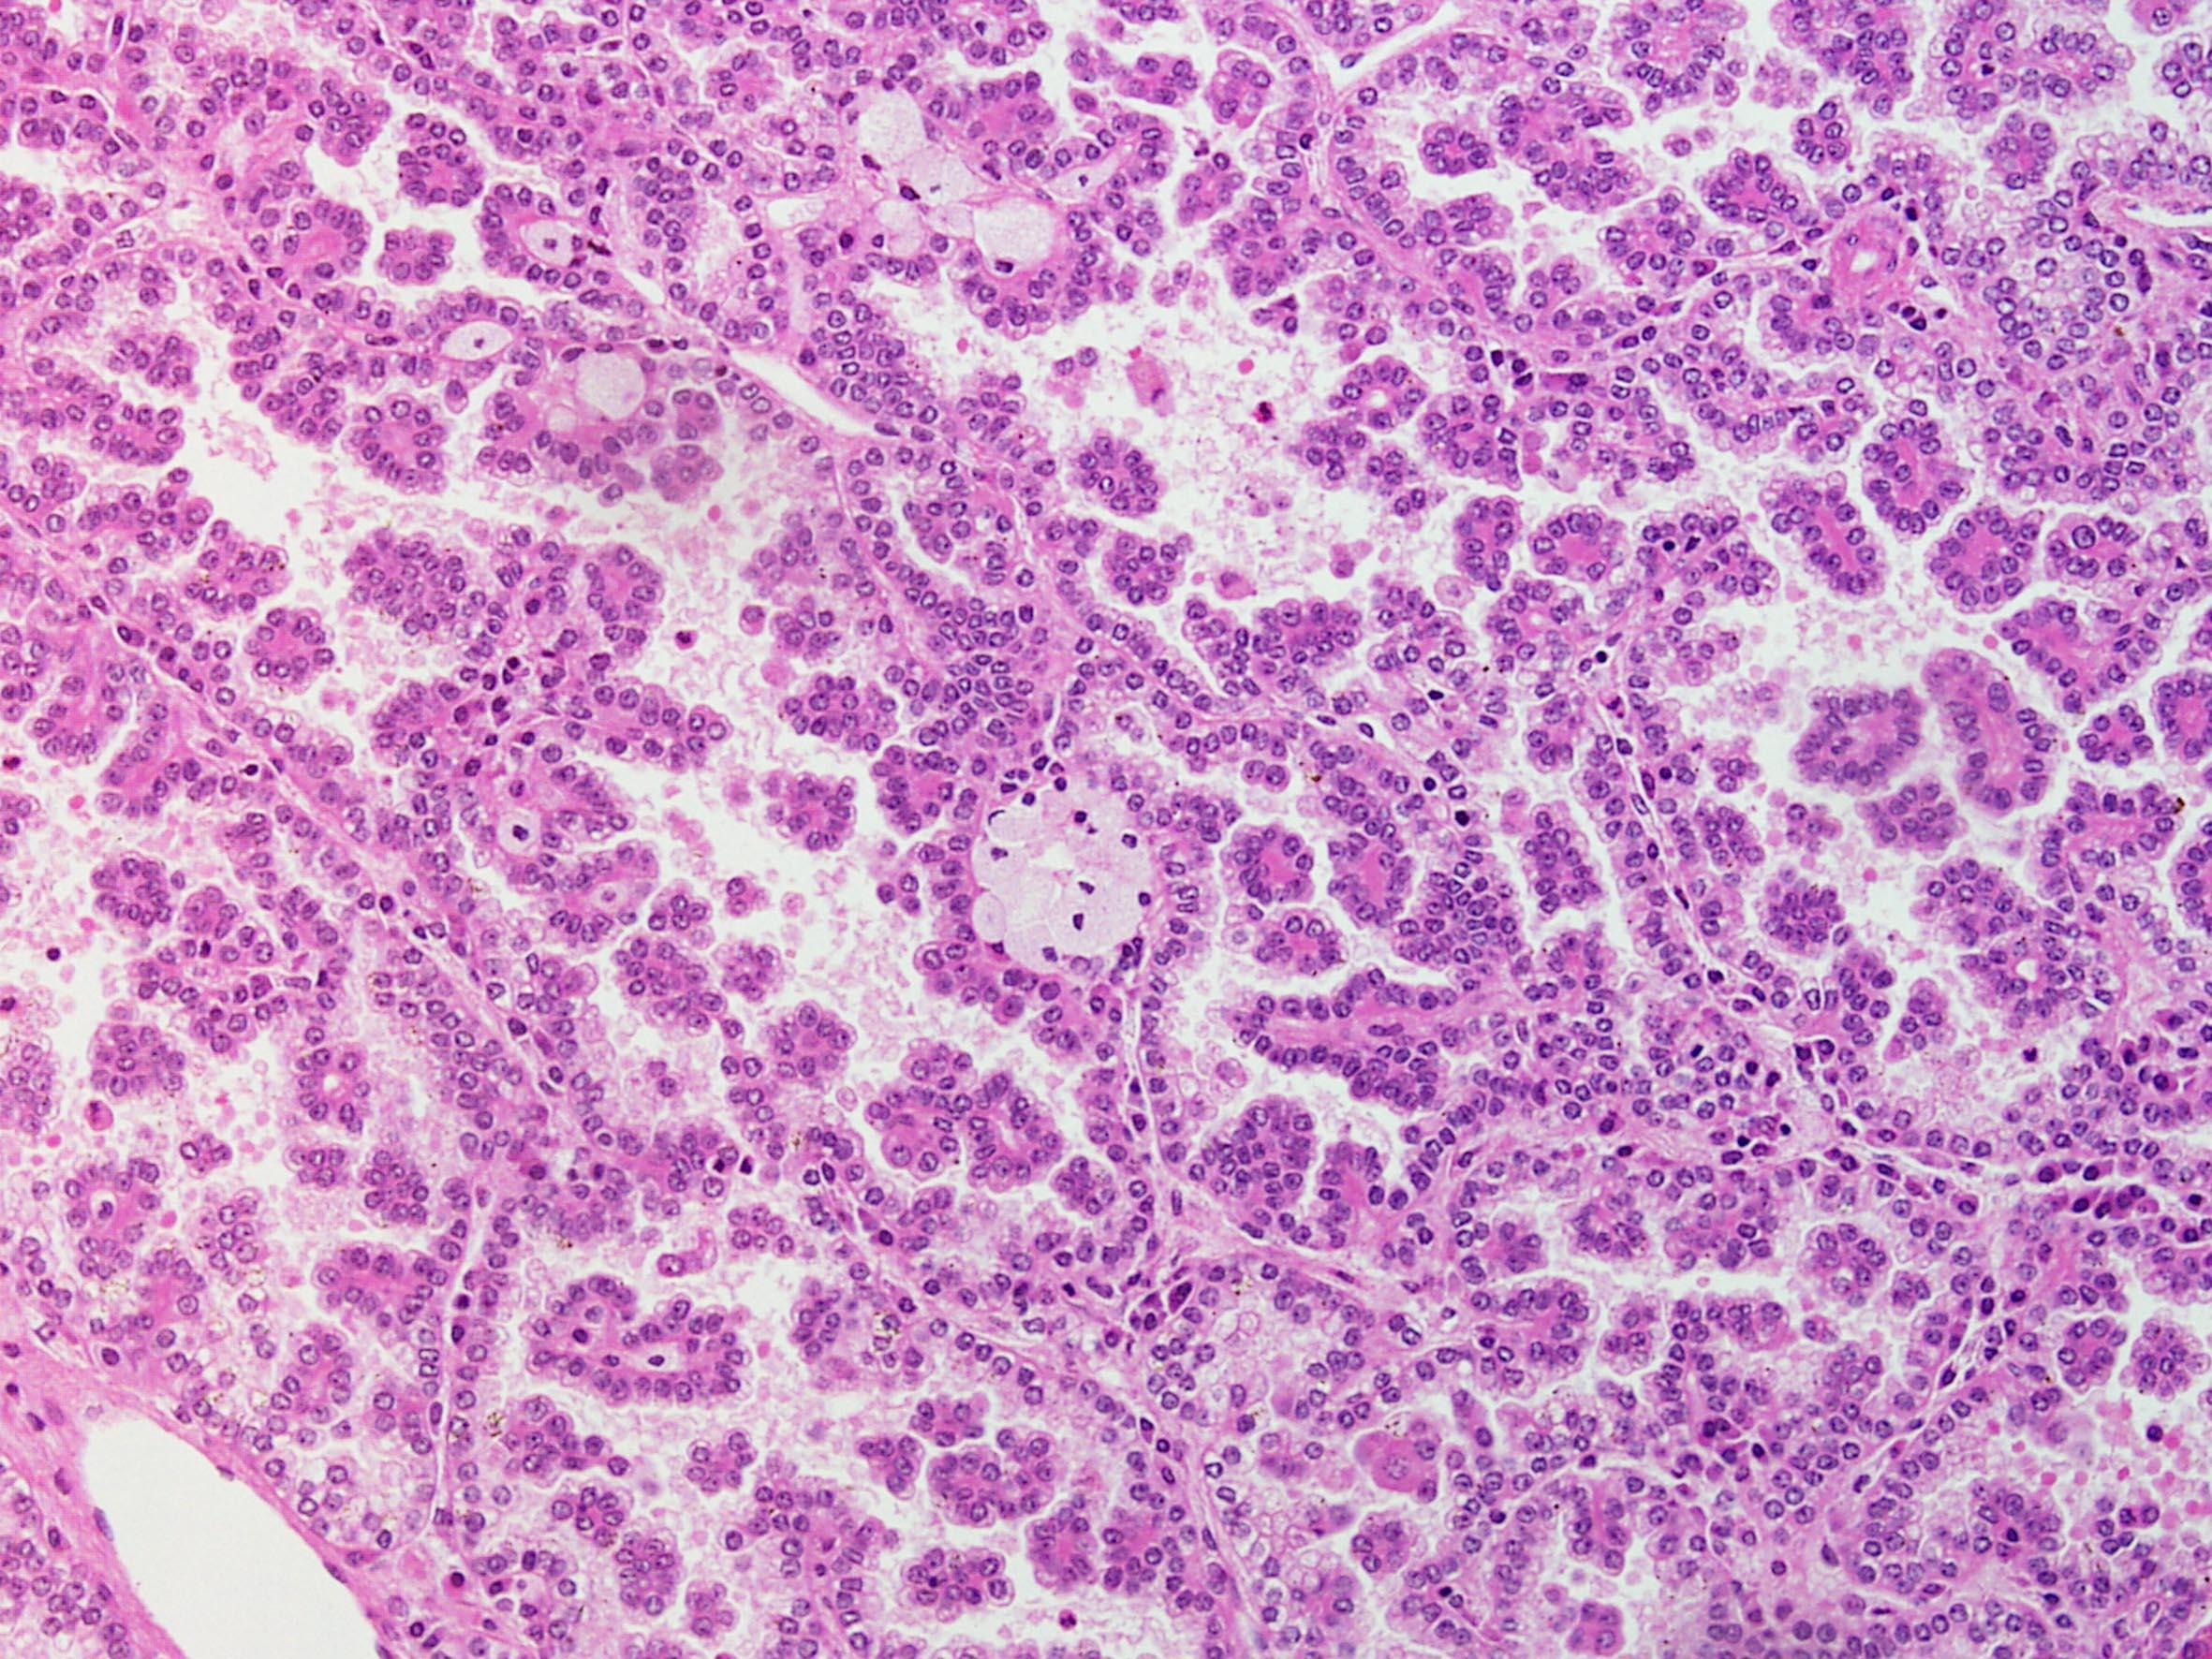

Classification of renal tumors

Case ID: 148